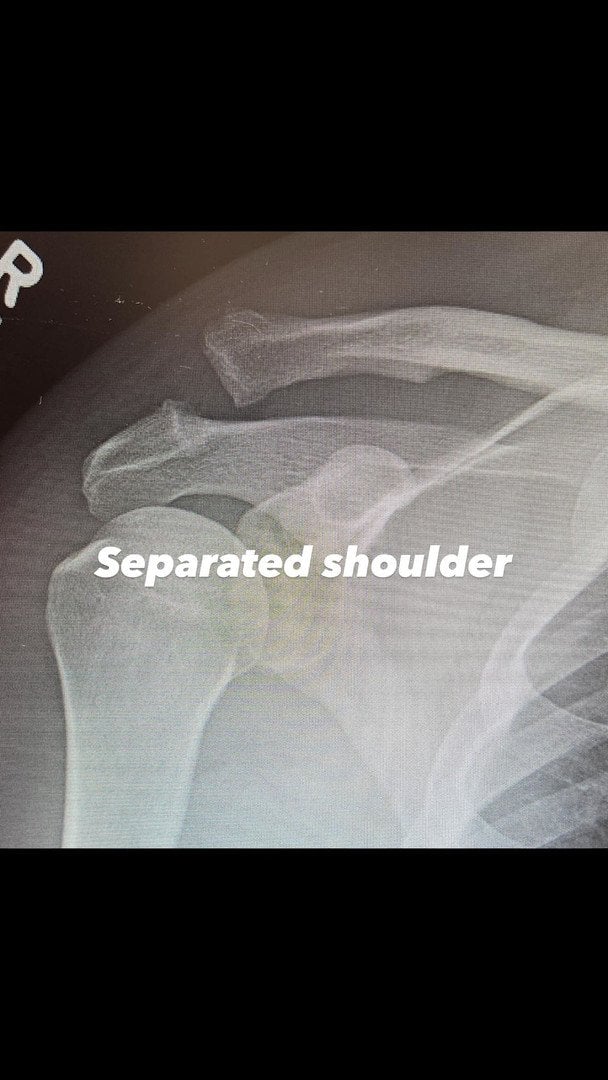

Як виявилося, Ченнінг Татум переніс операцію. Хірургічне втручання акторові знадобилось на плечі, оскільки він дістав серйозну травму. В актора вивих акроміально-ключового суглоба. Аби вправити плече на місце, довелося робити операцію.

Ченнінг Татум вже показав рентгенівський знімок до та після хірургічного втручання. Актор не став розкривати, як саме дістав травму, а лиш запевнив, що впорається зі всіма негараздами, хоч це й буде нелегко.